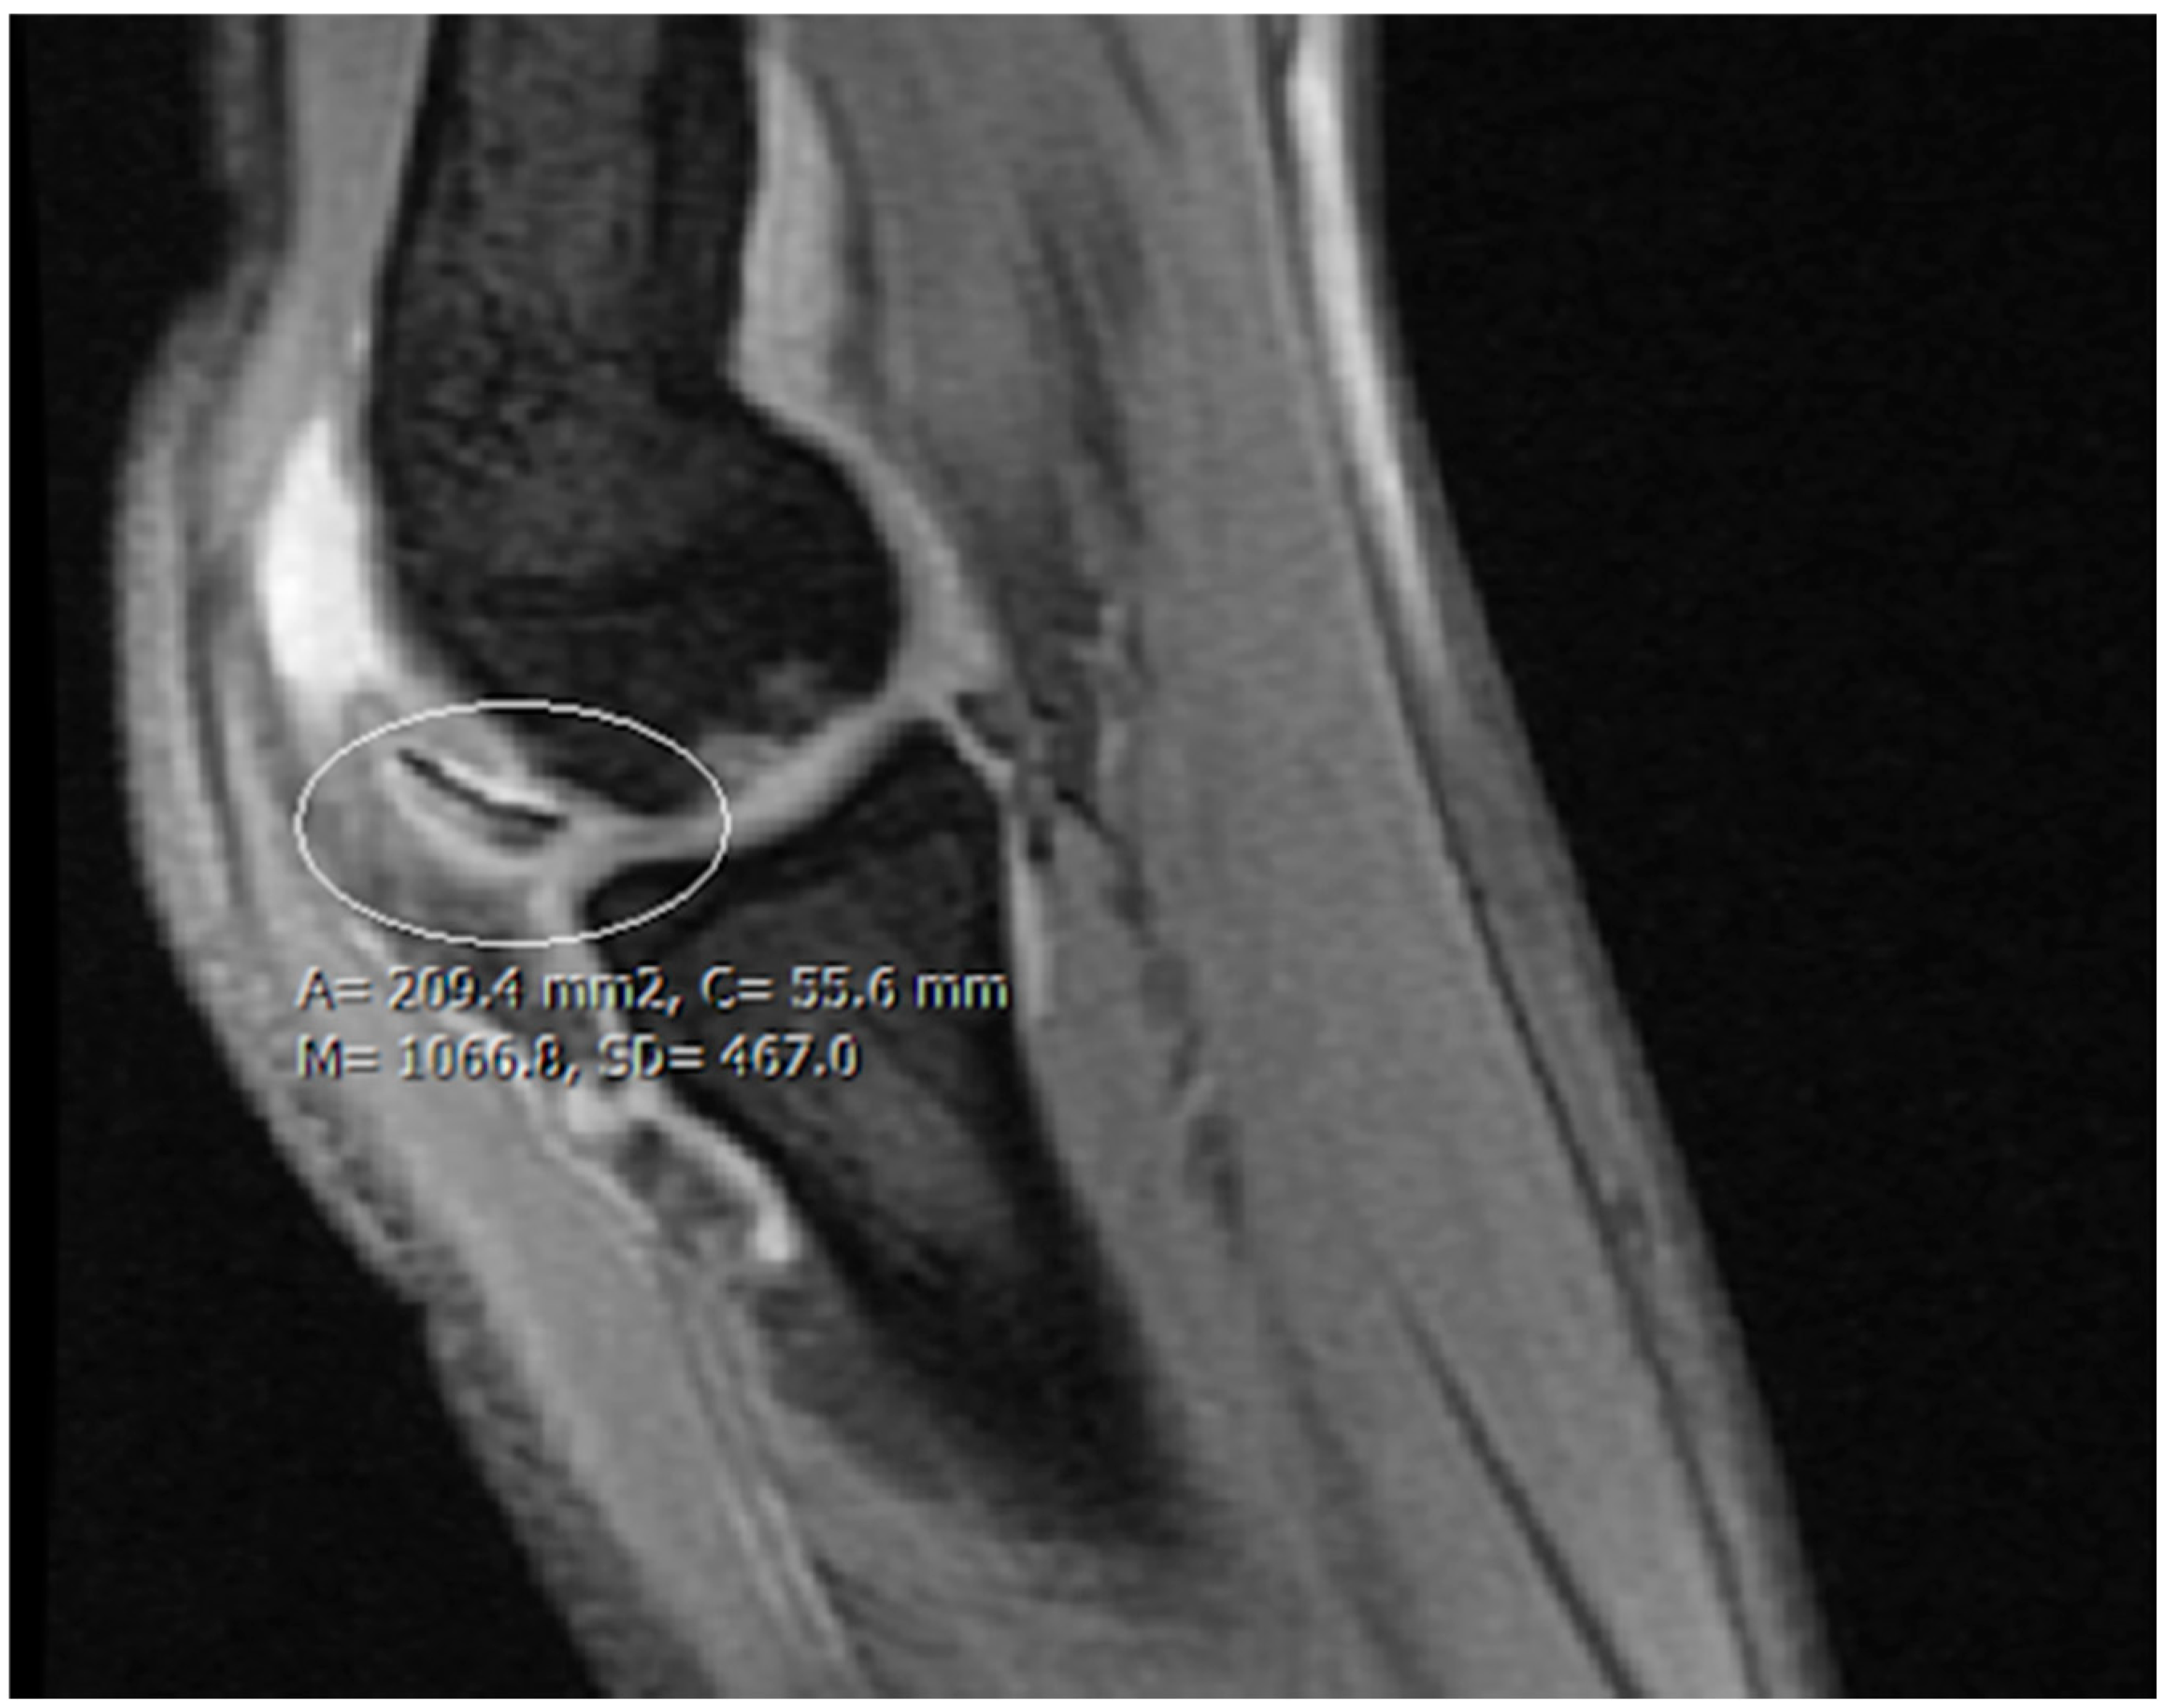

| Imaging: | X-ray | Arthroscopy | MRI | |||

|---|---|---|---|---|---|---|

| Classification | Berndt and Harty [21]—1959 | Guhl [22]—1982 | ICRS by Brittberg and Winalsky [23]—2003 | DiPaola [24]—1991 | Hefti [4]—1999 | Ellerman [15]—2019 |

| Stage 1 | Small subchondral compression | Intact Lesion | A stable lesion of the softened area covered by intact cartilage | Thickening of articular cartilage and low signal changes | Small change in signal, without clear fragment margins | Epiphyseal cartilage lesion with necrotic center |

| Stage 2 | Partially detached osteochondral fragment | A lesion with signs of early separation | Lesions with partial discontinuity which are stable when probed | Articular cartilage is breached, with a low signal rim behind the fragment indicating fibrous attachment | Osteochondral fragment with clear margins, without fluid in between | Epiphyseal cartilage lesion with complete or incomplete rim calcification |

| Stage 3 | Completely detached, non-displaced | Partially detached lesion | Lesions with complete discontinuity which are not dislocated (Dead in situ) | High signal changes behind the fragment indicate synovial fluid between the fragment and the underlying subchondral bone | Fluid is partially visible between the fragment and bone | Partially or completely ossified lesion |

| Stage 4 | Completely detached and displaced—loose body | Craters with loose bodies (salvageable or non-salvageable) | Empty defect bed with loose or dislocated fragment | Loose body | Fluid surrounds the fragment but it is still in situ | Healed osseous lesion with scar |

| Stage 5 | Scranton and McDermott modification: Subchondral Cyst | - | - | - | The fragment is completely detached and displaced | Unhealed, detached osseous lesion (Sequestrum) |